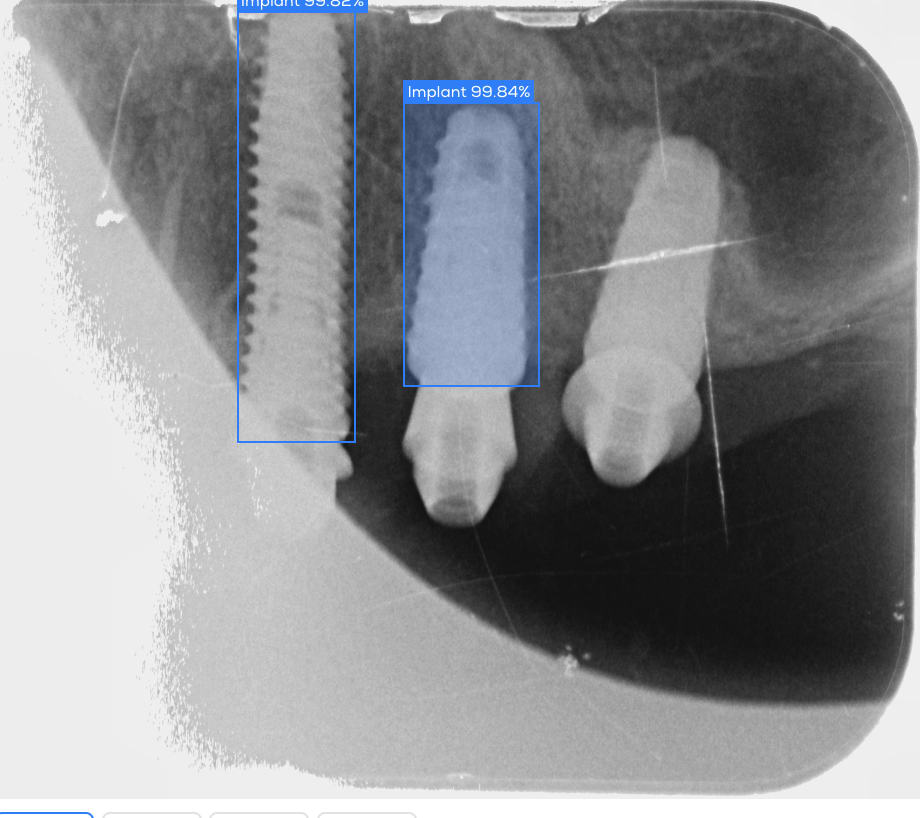

A priori ce praticien a posé plusieurs marques d'implants (Straumann victory tbr ankylos) et je pense qu'il s'agit de dentium. Pour m'en assurer j'ai fait une recherche par spot implant qui me le confirme. Probleme : j'ai contacté dentium leur ai envoyé les photos en leur demandant de me confirmer mon hypothèse et éventuellement de me donner le modèle d'implant pour commander l'accastillage et les scanbodies pour piliers MU. reponse de Dentium : "ce n'est pas un implant dentium crdt" je leur ai demandé d'argumenter car cela y ressemble et je n'ai actuellement aucune réponse (je pense que la photo des piliers MU les a fait shifter) donc avant de commander par moi meme je voulais avoir un avis de poseur dentium.

https://www.spotimplant.com/fr/identification/SmLQVh4r3AfwjdQXyGme9i/result

je ne sais pas si le rapport va etre lisible donc je le mets la

clairement des dentium....

mais le plus à gauche doit être une première génération